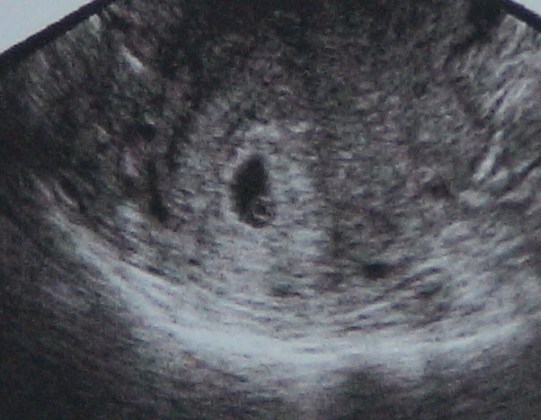

Hadd mutassam be "Kiskörtét"! Az egész kép a méhem, azon belül a fekete folt a petezsák, és abban a pici karika (látszik?) az pedig a szikhólyag. Na, abból lesz majd valaki! :D (később még jövök)

Kép Kiskörte